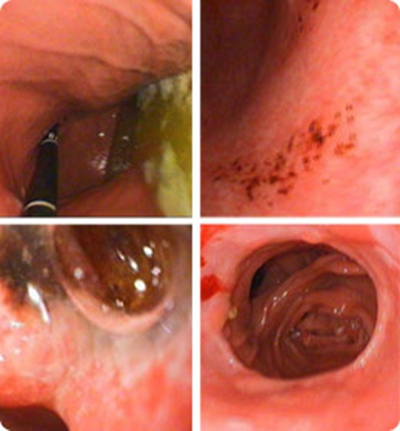

食道炎圖片